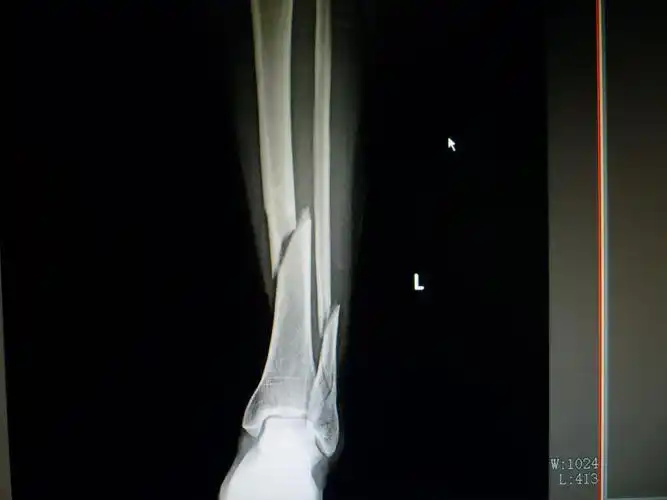

三例胫腓骨远端骨折